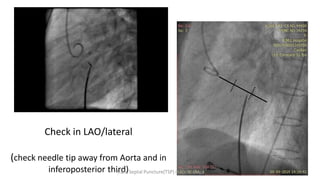

Check in LAO/lateral

(check needle tip away from Aorta and in

inferoposterior third)